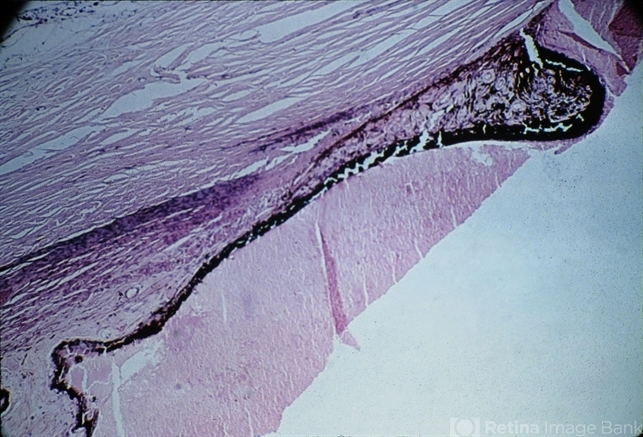

- sequelae, anterior synechiae, ectropion uveae

- Sequelae. Massive peripheral anterior synechia and ectropion uveae have resulted from blunt trauma. Note the postcontusion deformity of the anterior chamber angle (H&E x40).